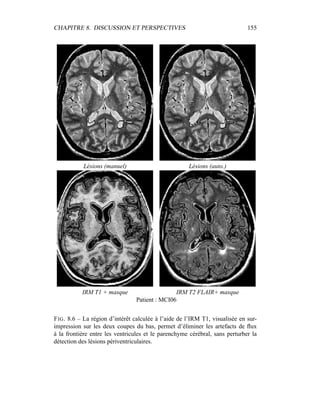

bélisation sur cette image en 2 classes. L’interface entre ces deux classes prend la

forme d’une sinusoïde, et ce afin d’accentuer la longueur de l’interface par rap-

port à la surface occupée par chacune des classes (figure 5.1). D’un point de vue

pratique, cette image est construite en haute résolution (3000*3000 pixels), et la